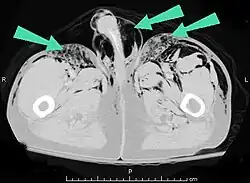

Les cas importants d'emphysème sous-cutané sont faciles à diagnostiquer en raison des signes caractéristiques de l'affection. Dans certains cas, les signes sont subtils, ce qui rend le diagnostic plus difficile. L'imagerie médicale est utilisée pour diagnostiquer la maladie ou confirmer un diagnostic établi à l'aide de signes cliniques. Sur une radiographie du thorax, l'emphysème sous-cutané peut être vu comme des stries radiotransparentes dans le modèle attendu du groupe de muscles principaux du pectoral. L'air présent dans les tissus sous-cutanés peut interférer avec la radiographie du thorax, ce qui peut masquer des affections graves comme le pneumothorax. Elle peut également réduire l'efficacité de l'échographie thoracique. D'autre part, comme l'emphysème sous-cutané peut être visible sur les radiographies du thorax avant un pneumothorax, sa présence peut être utilisée pour déduire celle de cette dernière lésion. L'emphysème sous-cutané peut également être observé sur les scanners, les poches d'air apparaissant comme des zones sombres. Le scanner est si sensible qu'il permet généralement de trouver l'endroit exact d'où l'air pénètre dans les tissus mous. En 1994, M. T. Macklin et C. C. Macklin ont publié d'autres aperçus sur la physiopathologie du syndrome de Macklin spontané survenant à la suite d'une grave crise d'asthme. La présence d'un emphysème sous-cutané chez une personne qui semble très malade et fébrile après une crise de vomissements suivie d'une douleur thoracique gauche est très évocatrice du diagnostic du syndrome de Boerhaave, qui est une urgence vitale causée par une rupture de l'œsophage distal. L'emphysème sous-cutané peut être une complication de l'insufflation de CO2 avec la chirurgie laparoscopique. Une augmentation soudaine du CO2 en fin de marée après la hausse initiale qui se produit avec l'insufflation (les 15-30 premières minutes) devrait faire suspecter un emphysème sous-cutané. Il est à noter que l'oxymétrie de pouls et la pression des voies aériennes ne varient pas dans l'emphysème sous-cutané, contrairement à l'intubation endobronchique, au capnothorax, au pneumothorax ou à l'embolie au CO2.